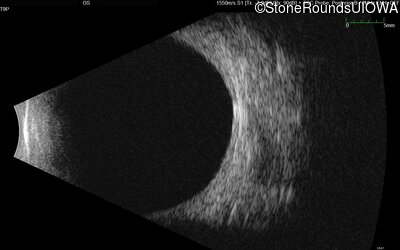

B-Scan Ultrasonography - Left - Light Perception

Exemplar